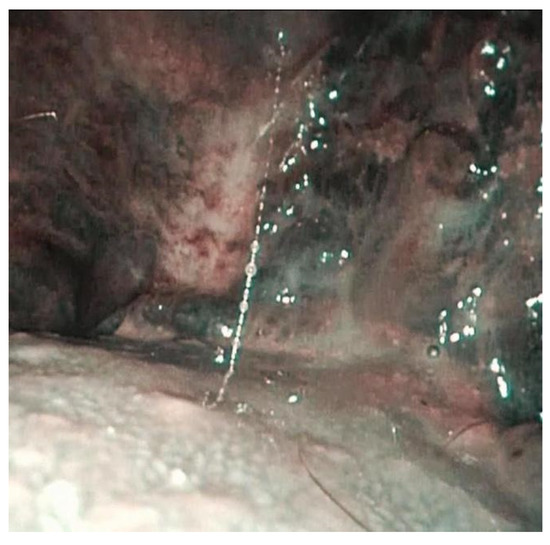

| 2 | Buccal mucosa bilaterally and left tonsillar pillar with extension at amygdalo-glossus sulcus and oropharynx | Erythroplakia paired with central erosive area | Diffuse mucositis and evidence of erythroplakia with erosive central area suspicious for malignant disease | Evidence of intrapapillary capillary loops | Squamocellular carcinoma of the oropharynx. |

| 3 | Right buccal mucosa and lateral right surface of the tongue. | Leukoplakia of the right surface of the tongue with an indurated area in the lower portion. | Reticular lichenoid-like lesions on the right buccal mucosa without suspicious of malignancy | Evidence of intrapapillary capillary loops. | Epitelial verrucous hyperplasia |